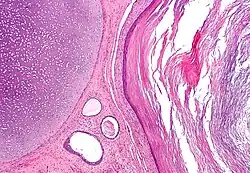

Dermoid cyst

A dermoid cyst is a mature cystic teratoma containing hair (sometimes very abundant) and other structures characteristic of normal skin and other tissues derived from the ectoderm. The term is most often applied to teratoma on the skull sutures and in the ovaries of females.

Mature teratoma

A mature teratoma is a grade 0 teratoma. They are highly variable in form and histology, and may be solid, cystic, or a combination of the two. A mature teratoma often contains several different types of tissue such as skin, muscle, and bone. Skin may surround a cyst and grow abundant hair . Mature teratomas generally are benign, with 0.17–2% of mature cystic teratomas becoming malignant.[18]